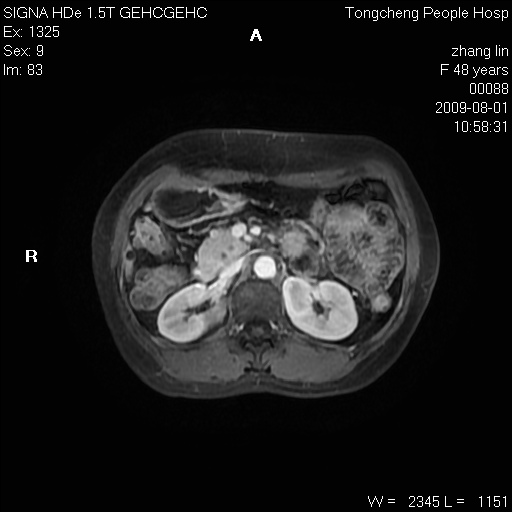

女,48岁。健康体检,彩超发现右肾占位性病变。平素健康。

临床诊断:右肾占位性病变,性质待定(囊肿?肿瘤?)。

上中腹部mr平扫+增强扫描,图像如下:

右肾上极见一类圆形病灶,t1wi呈等信号t2wi呈等高混杂信号,三期增强无强化,边界清---考虑囊肿出血。

同反相位均表现为等信号,病变无强化,考虑含蛋白的囊肿可能,弥散加权相或许有些帮助,

肝囊肿

慢性胆囊炎